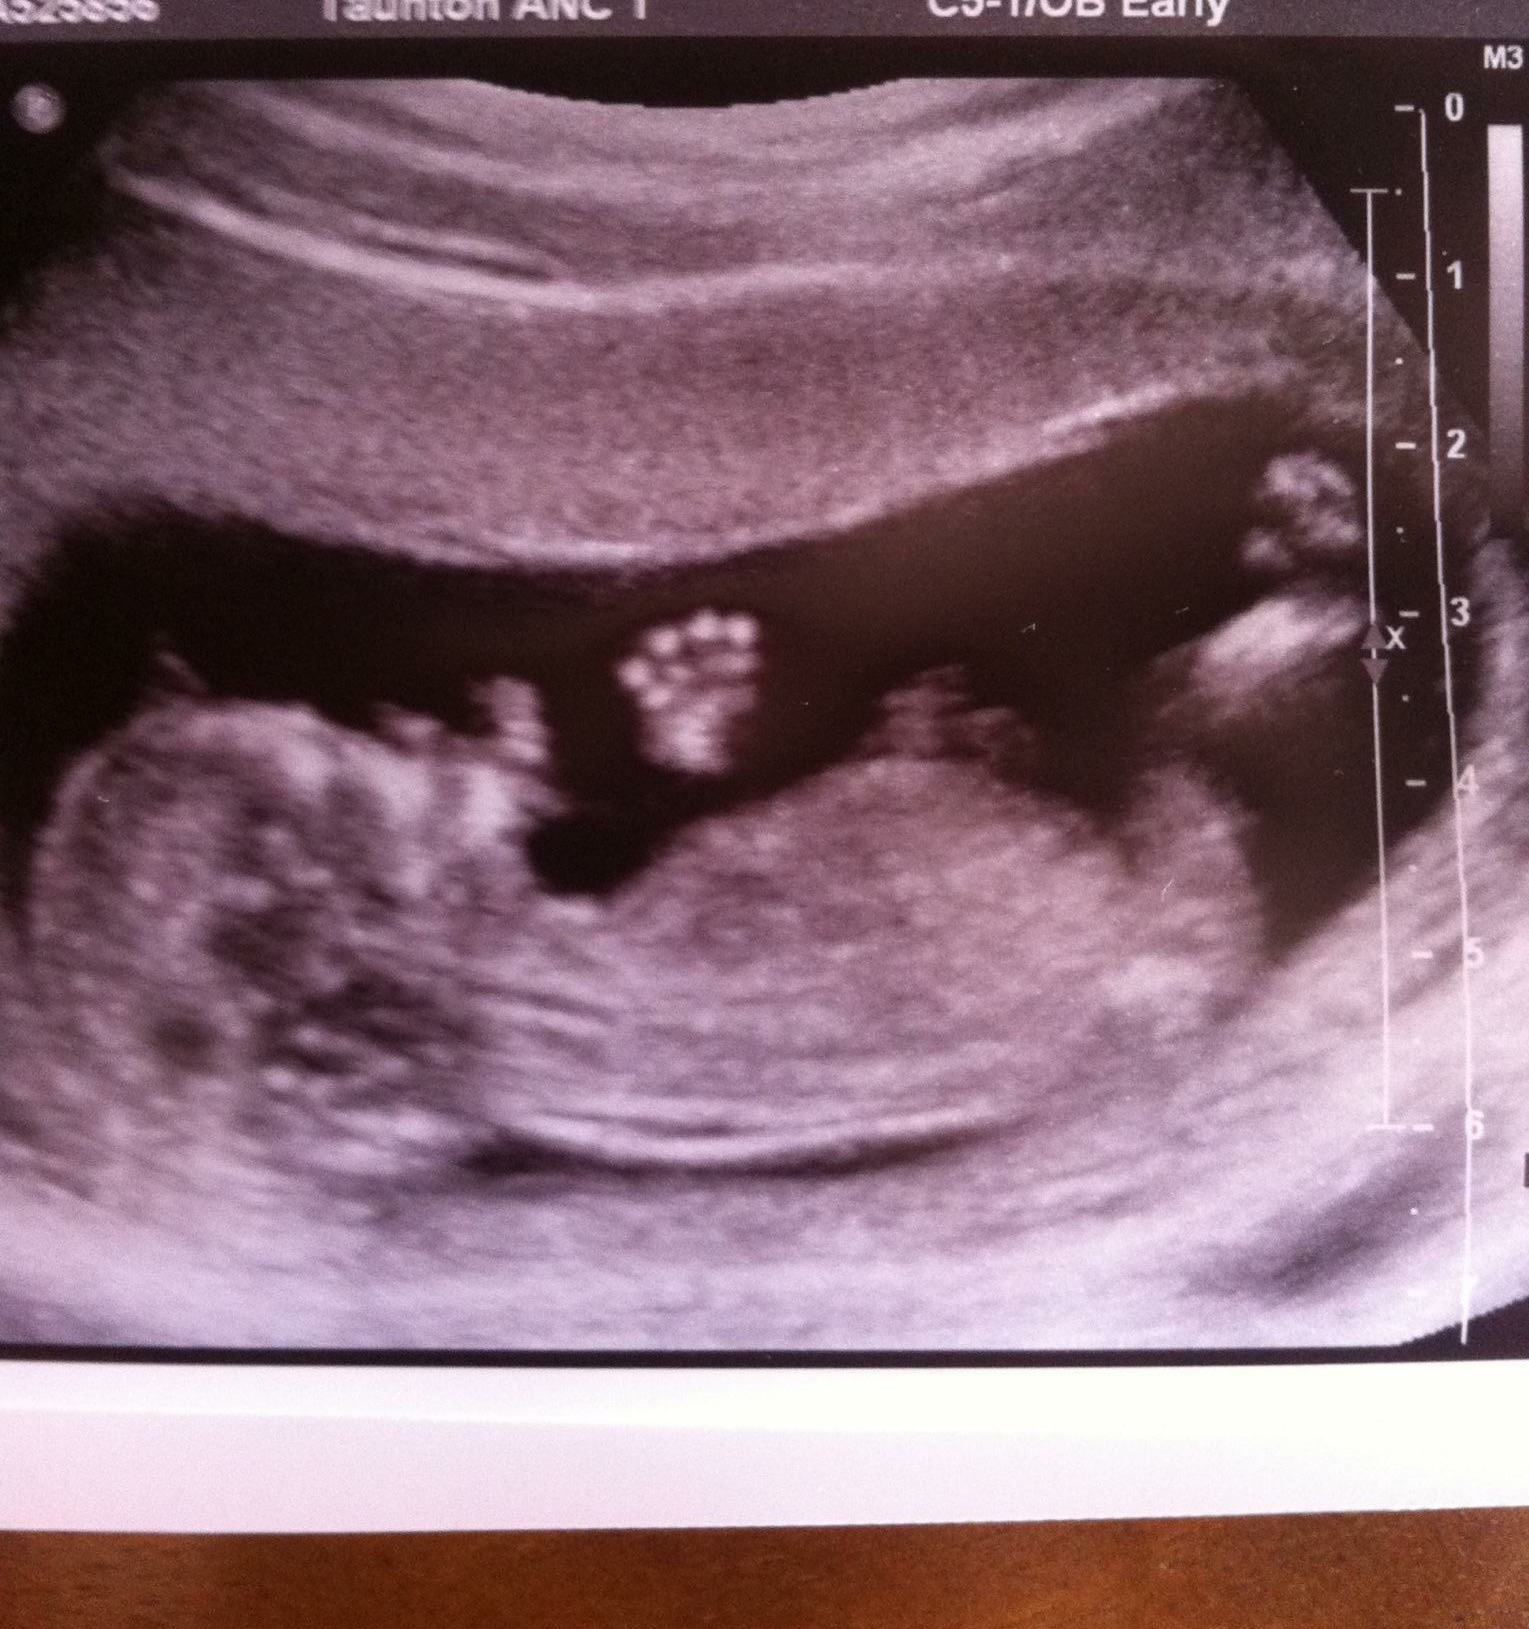

Here are my ultrasound pics taken at 12 + 2. I would really appreciate some gender guesses, going quietly crazy wondering what this baby could be! I've got an idea but would love some other peoples' views.

10 days until our gender scan and I cannot wait! Thanks in advance xxAttachment 24131Attachment 24132